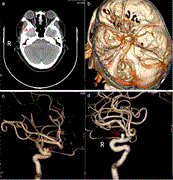

Temporal lobe meningioma concurrent with multiple intracranial aneurysms

Xia Wu and others

Journal of Surgical Case Reports, Volume 2021, Issue 2, February 2021, rjaa581, https://doi.org/10.1093/jscr/rjaa581